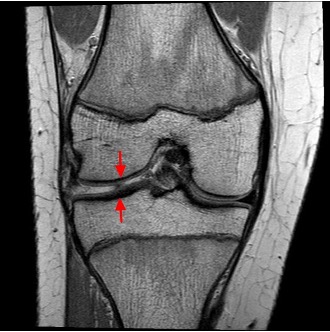

Today began with consultations with surgeon Dr. AH. The first patient was (R), a 5-year-old girl who had exhibited bilateral toe walking from a young age. She also frequently experiences inflammation and restricted movement in her left knee. Dr. AH shared the results of her X-ray with the mother, revealing that R had a complete lateral meniscus tear. This tear is located in the joint area between the femur and tibia. The meniscus is a disc shaped structure that helps facilitate smooth motion in the knee, and a complete meniscus tear is extremely rare in children, particularly at the age of 5.

Figure 3: MRI scan of Meniscus tear.

A major risk associated with this condition is the possibility of a locked knee, where the knee becomes stuck in motion because the torn meniscus gets caught. This would require immediate surgical intervention. However, there were currently no plans for surgery, though a potential MRI scan was discussed.